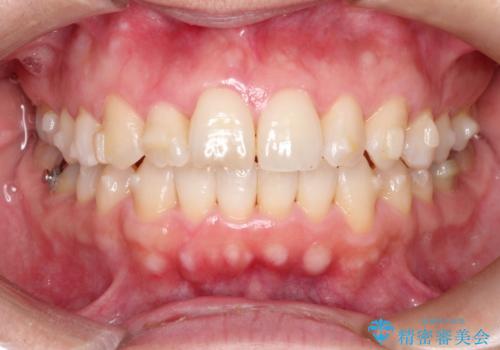

【インビザライン 】前歯のガタガタを治したい

- 前歯のガタガタを主訴に来院されました。

インビザライン で治療しました。途中は使用時間が20時間を切ることもありましたが、それでも頑張って使っていただき1年半で矯正終了することができました。